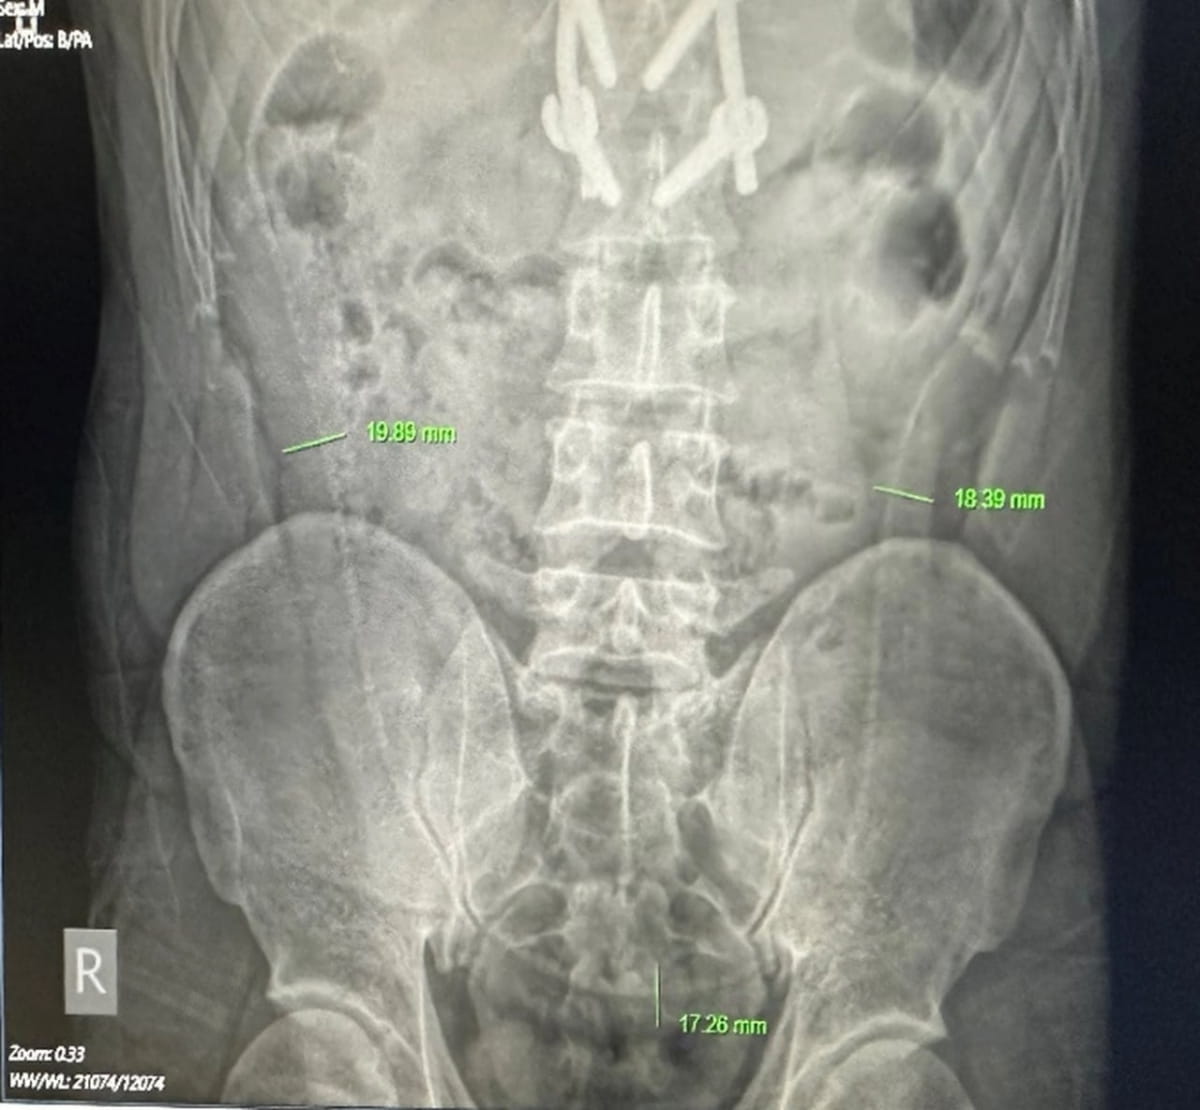

В больнице Viet Duc рентгеновское обследование обнаружило внутри пациента угря длиной 65 см, которого он засунул в тот же день, 27 июля. Снимок показал "длинную структуру", простирающуюся через живот.

Врачи установили, что боль была вызвана тем, что угорь пытался прогрызть себе путь наружу, прокусив толстую кишку мужчины. При попытке вытащить рыбу с помощью зонда медицинский персонал также нашел, что в анусе пациента был целый лимон.

Хирургам пришлось произвести разрез на животе, чтобы удалить угри щипцами, а лимон протолкнули назад через анус. После этого врачи зашили отверстие в кишечнике. Пациенту теперь придется жить с калоприемником, и медики отмечают, что без своевременного вмешательства он мог бы погибнуть.